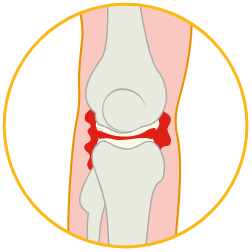

Nelle persone con emofilia, i sanguinamenti possono verificarsi nelle articolazioni, comunemente nei gomiti, nelle ginocchia e nelle caviglie.

Durante un sanguinamento articolare, il sangue entra nell’area tra le ossa dell’articolazione, un’area ricca di liquido, esercitando un’ulteriore pressione sull’articolazione.

I sanguinamenti articolari dovrebbero essere trattati rapidamente per ridurre il dolore e cercare di prevenire ulteriori danni.

Infatti, dopo numerosi sanguinamenti a carico della stessa articolazione:

- i tessuti importanti che proteggono l’articolazione sono danneggiati;

- i muscoli intorno all’articolazione possono indebolirsi;

- l’osso dell’articolazione può iniziare a rompersi;

Ciò provoca danni permanenti, perdita di movimento e dolore articolare grave e costante; per prevenire ulteriori danni, potrebbe essere necessario un intervento chirurgico per fissare l’articolazione in posizione o per sostituire l’articolazione. Il danno articolare può diminuire la capacità della persona con emofilia di prendere parte alle attività e può ridurre la sua qualità di vita.